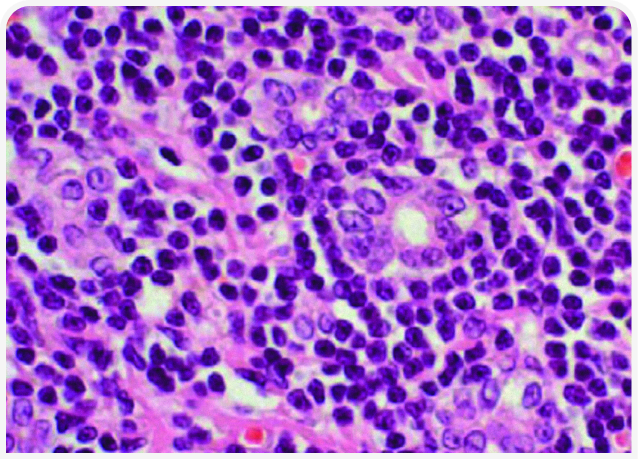

Лечение

После постановки окончательного (см. гистопатологическую картину на Рисунке 3) или предположительного (как в клиническом случае) диагноза «лимфоцитарный холангит» лечение будет включать неспецифическую поддерживающую терапию и иммунную терапию. К неспецифической терапии относятся инъекции нескольких доз витамина K1 (5 мг на кошку подкожно каждые 24 часа) для нормализации показателей свертывания крови перед проведением тонкоигольной аспирационной биопсии или установкой эзофагального зонда и урсодезоксихолевая кислота (10-15 мг/кг внутрь каждые 24 часа в течение 2-3 месяцев). Этот препарат традиционно используют для стимуляции выведения желчи из билиарной системы; он обладает также рядом дополнительных положительных свойств для пораженной ткани печени (21).

Специфическое лечение лимфоцитарного холангита заключается в назначении глюкокортикоидов, препаратом выбора считают преднизолон. Некоторые врачи начинают с дозы 4 мг/кг/день, большинство – с дозы ближе к 2 мг/кг/день, но во всех случаях дозу медленно снижают в течение 3 месяцев.